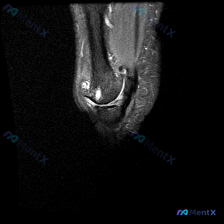

最近看到这例踝关节MRI读片讨论,问题是「图像中能观察到什么软组织液相关改变」,整理一下完整分析思路,分享给大家。 一、病例影像核心信息 这是踝关节MRI冠状位T2加权图像,核心发现如下: 1. 骨结构改变:胫骨远端、距骨、跟骨显影清晰,距骨穹窿内侧关节面可见局灶性高信号改变,边界清晰,呈楔形凹陷状...

踝关节MRI读片病例分享,整理了完整分析思路 这是一例踝关节矢状位T2加权MRI,我把影像发现和分析思路整理出来,和大家一起讨论。 一、基本影像信息 这是踝关节MRI T2序列矢状位图像,可观察到胫骨远端、距骨、跟骨及周围软组织结构,核心阳性征象如下: 1. 骨骼关节改变:距骨穹窿(圆顶)可见明确局...

病例影像读片分享 今天整理了一例踝关节MRI的读片资料,把分析思路分享给大家一起讨论。 基本影像信息 这是一张踝关节矢状位T2加权MRI,可以清晰显示胫骨远端、距骨、跟骨、舟骨、楔骨等踝关节复合体骨性结构,T2序列对液体信号显示清晰。 核心阳性发现 1. 多关节广泛积液:胫距关节前后隐窝、距下关节间...